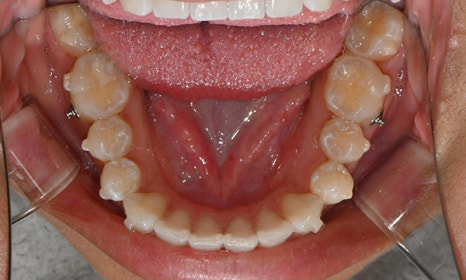

치아 상태는 어땠냐면요:

위아래 앞니 사이에 공간이 벌어져 있었어요.

앞니가 삐뚤빼뚤한 덧니도 있었죠.

윗니와 아랫니가 너무 깊게 맞물리는

과개교합이 있었어요.

왼쪽 아래 작은어금니가 90도 돌아가 있었는데,

이로 인해 왼쪽 치아 배열과 교합이 좋지 않았죠.

초진시 구내사진 (2025. 3.31)